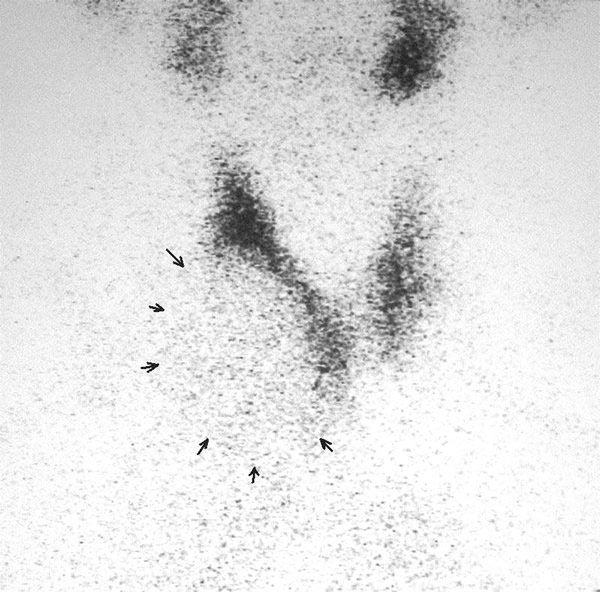

A 58-year-old Chinese man presented with a dry cough of three months’ duration. A chest x-ray at a local hospital revealed "a shadow in the superior mediastinum." A subsequent CT scan suggested "ectopic intrathoracic thyroid" (Figures 1 and 2). His physical examination revealed normal temperature and heart rate, without any signs of hyperthyroidism. Palpation of the neck revealed a non-tender, firm, fixed, and non-pulsatile 2 cm right inferior thyroid mass. A repeat chest x-ray confirmed a mass in the right anteromedial mediastinum, with smooth margins, tracheal compression, and deviation of the trachea to the left (Figure 3). Nuclear Tc99 thyroid scan revealed a cold nodule in the right inferior thyroid gland extending below the sternum (Figure 4). The values of total thyroxin 3 (TT3), total thyroxin 4 (TT4), free thyroxin 3 (FT3), free thyroxin 4 (FT4), and thyroid stimulating hormone (TSH) were all normal. Due to the suspicion of malignancy and to avoid the development of tracheomalacia, surgery was performed to remove the mass.